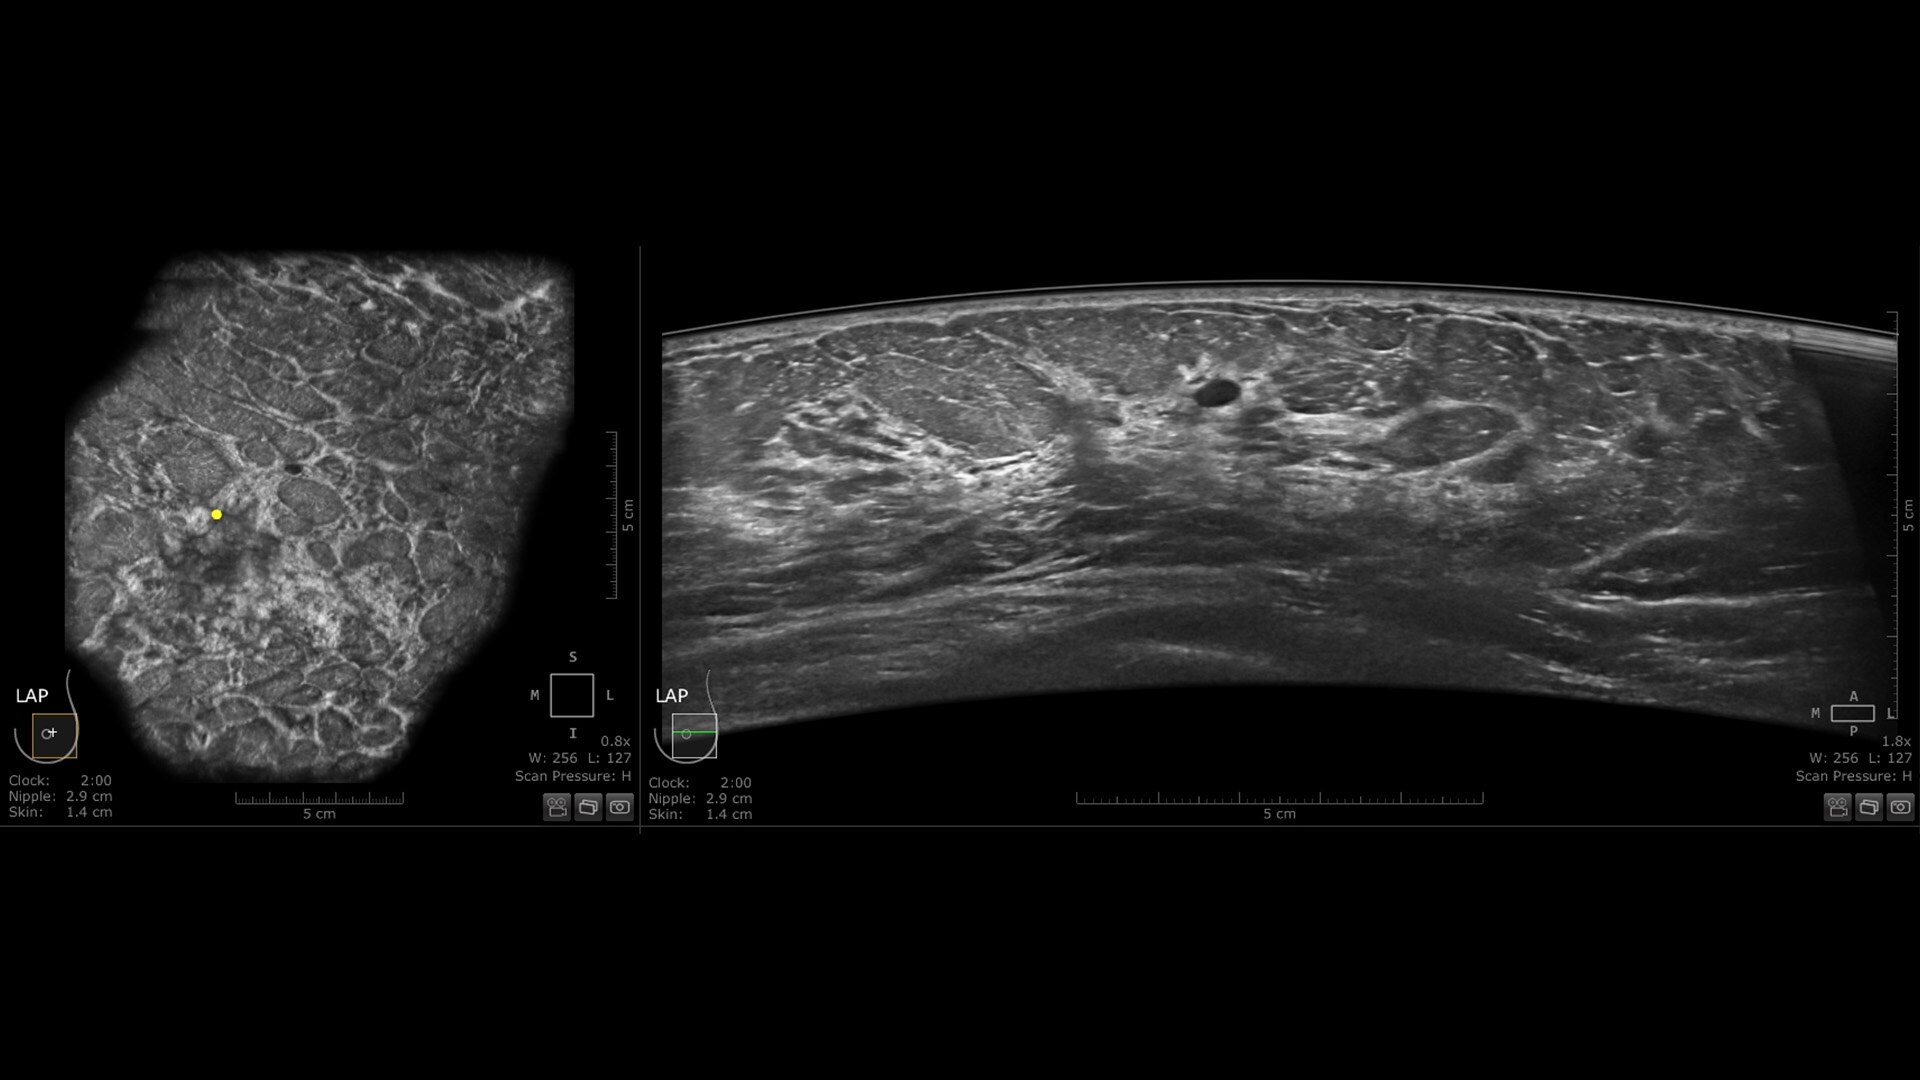

The Invenia ABUS Premium is designed for high patient throughput and extraordinary image quality to provide a great level of confidence. With its innovative design, it’s easy to use, reproducible, user-independent, standardized and allows reading anywhere.

The novel Reverse Curve™ transducer is designed for enhanced performance

Its gentle 15.3 cm shape follows the breast's natural contour, enhancing patient comfort* and ensuring full contact for comprehensive coverage. The improved image quality* increases diagnostic confidence for reading ABUS exams.

Excellent image quality and 40% faster scan speed

• cSound Imageformer, software-based processing, produces exquisite, reproducible images by leveraging automatic focus at every pixel.

• Fast Scan increases scan speed by 40%*, fostering improved efficiency and patient throughput.